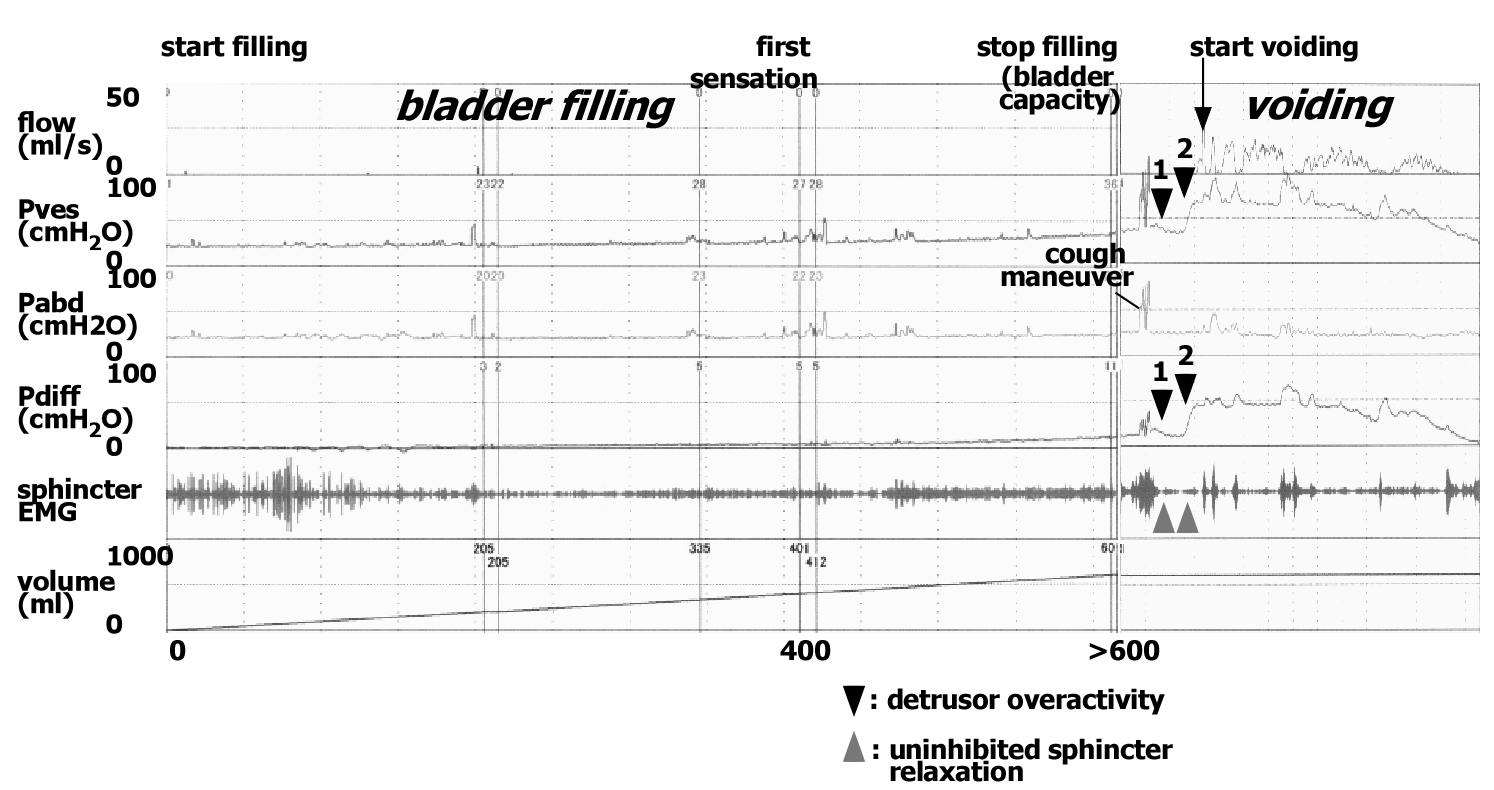

A young man with herpes simplex encephalitis: Andrew and Nathan type urodynamic abnormality

Abstract 152 | HTML Downloads 68 PDF Downloads 62 | DOI https://doi.org/10.14440/bladder.2014.25Page e4